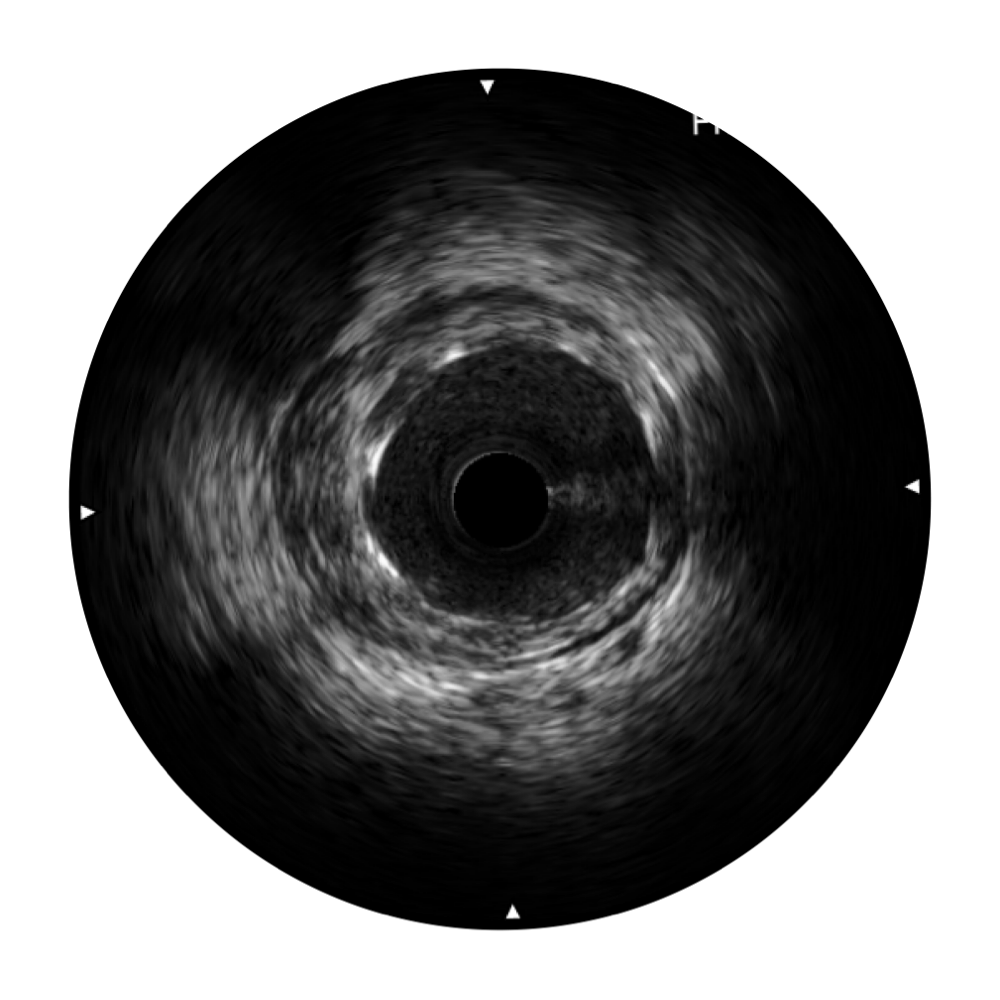

1xBET宽频IVUS图像

传统IVUS图像

对比传统IVUS导管成像,1xBET宽频IVUS图像的近场支架梁显影更细腻,远场中膜外血管仍清晰可辨,兼顾远中近,兼顾分辨力与穿透深度